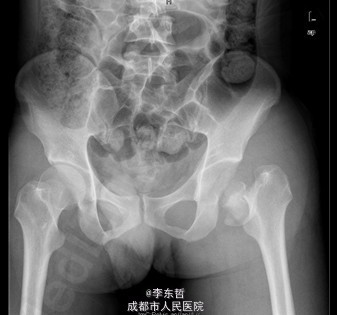

患者男,31岁,因“左股骨头股骨颈骨折切开复位内固定术后1+年”入院。患者1+年前因车祸致左股骨头、颈粉碎性骨折伴坐骨神经损伤于我院就诊,于我院行左股骨头股骨颈骨折切开复位空心钉+可吸收镙钉内固定术,术后恢复良好出院。术后8月后扶双拐活动。7月前患者无明显诱因出现左髋部疼痛,以负重时为重,后患者只能扶双拐活动。现患者为进一步治疗入我院。患病以来患者精神可,食欲可,睡眠可,大小便未见明显异常,体重无明显变化。

查体:T:36.2oC,P:80次/分,R:20次/分,BP:112/74mmHg。神志清楚,无病容,皮肤巩膜无黄染,全身浅表淋巴结未见肿大。颈静脉搏动、心界正常,心律齐,各瓣膜区未闻及杂音。胸廓未见异常,双肺叩诊呈清音,双肺呼吸音清,未闻及干湿啰音及胸膜摩擦音。腹部外形正常,全腹柔软,无压痛及反跳痛,腹部未触及包块,肝脏肋下未触及,脾脏肋下未触及,双肾未触及。双下肢无水肿。视:左髋外侧可见一约30cm手术瘢痕,其上可见一点状结痂,左腿较右腿短缩,左腿肌肉较右腿萎缩,步态异常。触:左髋部无压痛,左腿外侧感觉异常,以左膝外侧为重,左髋外侧叩击痛,左足背动脉搏动未扪及异常。动量:左下肢较右下肢短缩约3cm,左髋关节活动受限,其余各关节未见明显异常。

入院诊断:左股骨头股骨颈粉碎性骨折切开复位内固定术后坏死;积极完善术前检查及准备后行关节置换术。